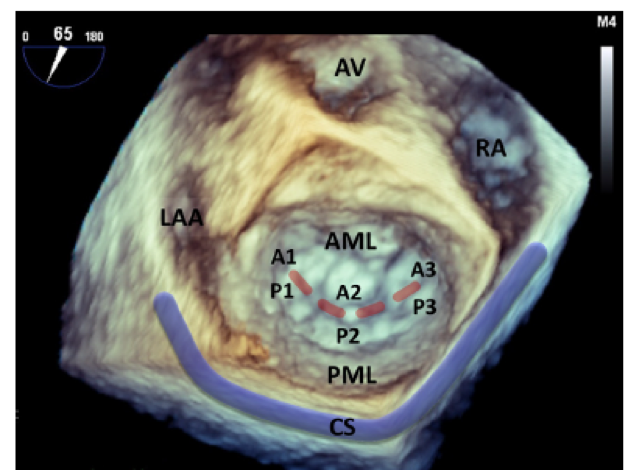

二尖瓣是一个复杂的结构(如图1),由瓣环、前叶、后叶、腱索、前外侧和后内侧乳头肌(PM)组成。1983年,Carpentier描述了基于瓣叶运动的MR功能分类(如图2)。MR的另一个分类是原发性(退行性)和继发性(功能性),尽管病理可能共存。原发性MR的病理学表现为瓣膜的一个或多个组成部分,粘液瘤变性导致二尖瓣(PV)脱垂是主要原因。继发性MR是由于左心房(LA)或左心室(LV)功能和几何结构的改变导致的瓣叶错接的结果,可以进一步细分为缺血性和非缺血性MR。缺血性MR主要与局部室壁运动异常相关,导致乳头肌(PM)移位和瓣叶栓系(Carpentier IIIb型),通常导致偏心性MR。非缺血性MR的主要机制是继发于左心房(LA)或左心室(LV)增大(Carpentier I型)的环状扩张,导致中央方向的反流。在欧洲MR登记册中,MR的病因原发性的为55%,继发性的为30%,混合的为14%的中度或重度MR患者。

图1:二尖瓣的三维经食管超声心动图心房视图。红色虚线:二尖瓣口。A1-3:前叶;AML,二尖瓣前叶;AV:主动脉瓣;CS:冠状窦;LAA:左心耳;P1-3:后小叶;PML:二尖瓣后叶;RA:右心房。